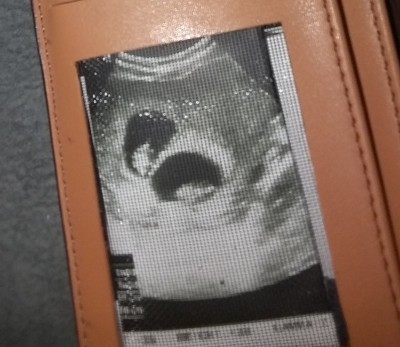

Canım daha çok erken ikiz gebelik olsa bile simdi belli olur mu bilmiyorum ben çok benzetemedim ama rabbim hayırlısını versin benim de Ikiz ve bu ultrasonum 7 haftalık çekilmişti bir bak istersen.